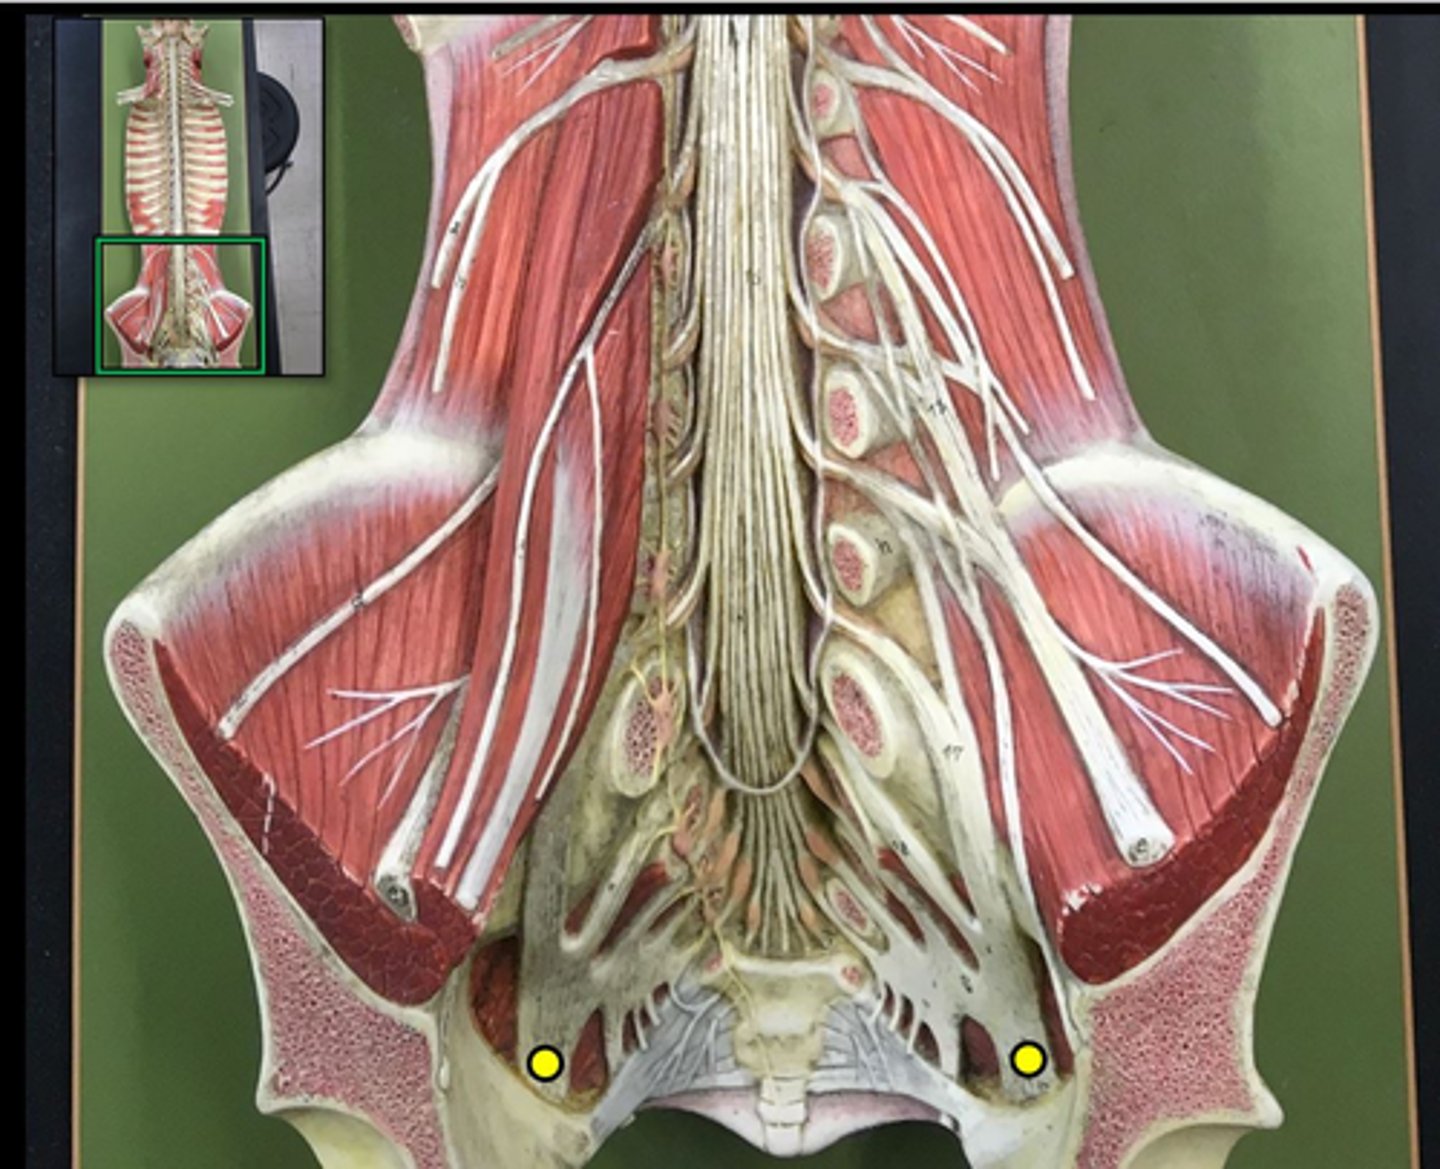

cauda equina

bundle

lumbar plexus

T12- L4

sacral plexus

L4- S4